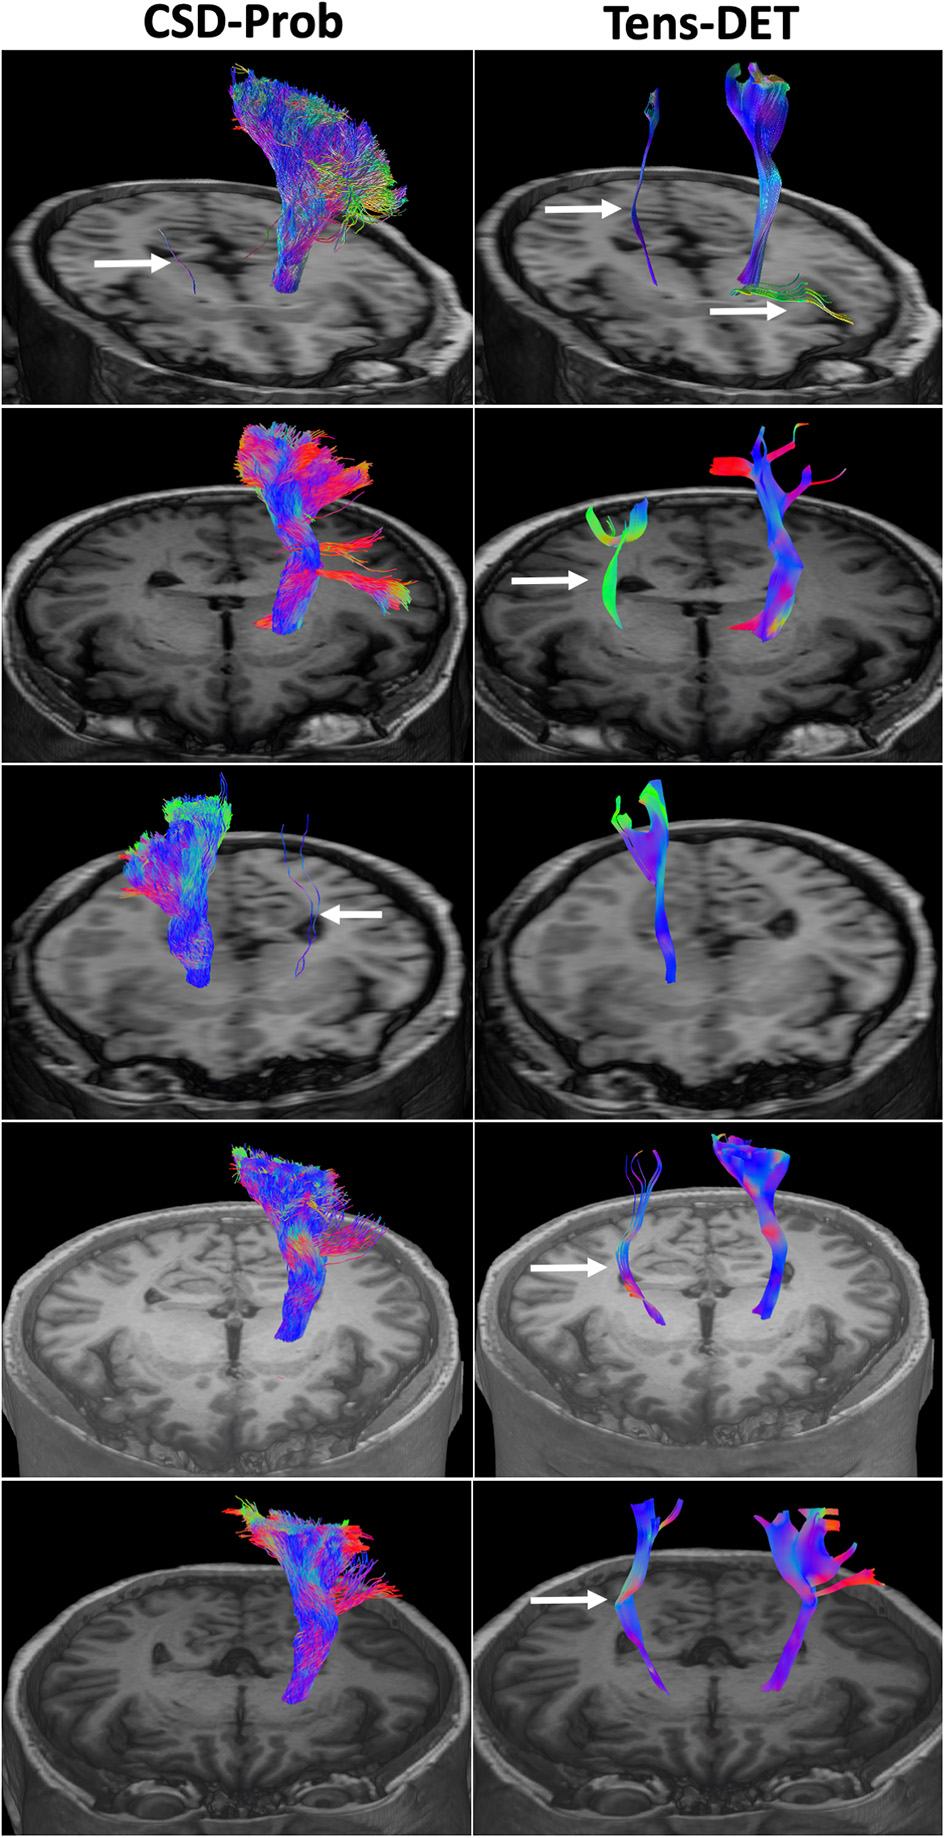

Figure 3

Comparison of the CSD-Prob and Tens-DET approaches in 5 subjects. The left panels show the 3D reconstruction of the CST by the CSD-Prob with the fan-like configuration of the cortical projections of the CST. The right panels show the CST by the Tens-DET approach with a straight trajectory to the dorsal part of the precentral gyrus, absence of the ventral part of the motor CST, and more prevalence of spurious fibers than the CSD-Prob (arrows).

We included 12 patients, six men and eight women with a mean age of 50 years (detailed clinical and demographic data are shown in Table 1). Pathological results yielded WHO grade II glioma in four patients and WHO IV glioblastoma (GBM) in eight patients. Preoperatively, six patients were neurologically intact and six presented with mild motor deficit (grade 4/5). Gross total resection was achieved in 9 patients. The CST was identified in all patients with the two tractography approaches with different patterns of displacement (Figure 2). The CSD-Prob approach showed the CST with the characteristic fan-like configuration from the dorsal and ventral precentral gyrus to the brainstem. The Tens-DET approach showed a straight trajectory from the dorsal precentral gyrus to the brainstem missing the ventral part of the precentral gyrus. This approach also underestimated the width of the CST and showed more spurious streamlines as compared with the CSD-Prob approach (Figure 3). Among the six patients with postoperative motor deficit, the CSD-Prob approach revealed CST disruption in different degree, and this was strongly associated with the degree of motor deficit in these patients (rho = −0.88, p = 0.021). The Tens-DET approach on the other hand, showed disruption of the CST in five of the six patients with motor deficit without significant association in the motor status (rho = −0.27, p = 0.6) (Table 1, Figure 4). Finally, only the CSD-Prob identified a significant decrease in fractional anisotropy (p = 0.0006) and an increase in mean and radial diffusivity (p = 0.004, 0.005) of the CST between the ipsilesional and the contralesional hemisphere (Figure 5). There was no significant difference in the axial diffusivity with the CSD-Prob approach and with none of the diffusion scalars with the Tens-DET approach.

The CST was generated by two different tractography techniques in the setting of brain tumor and peritumoral edema. The CSD-Prob approach has demonstrated accuracy in the representation of the CST as previously demonstrated (9). The CSD-Prob also showed a meaningful reconstruction of the CST since there was a consistent degree of CST disruption significantly correlated with postoperative motor deficit. The Tens-DET approach showed limited accuracy to generate the CST with more spurious streamlines than the CSD-Prob approach. Most of these spurious streamlines originated at the level of the brainstem and continued propagating to the contralateral side following different bundles including contralateral CST, cerebellum, and optic radiations. This may be related with a more prevalence of crossing fibers in the brainstem and the difficulty of the Tens-DET to resolve crossing fibers. Modifications in the tracking parameters of the Tens-DET approach could have minimized the presence of these spurious streamlines but the comparison of different tracking parameters in the Tens-DET approaches is beyond the scope of this article. In three of the six cases with postoperative motor deficit, the disruption of the CST defined by the Tens-DET approach was not consistent with the degree of motor deficit, likely due to the missing parts of the ventral precentral gyrus. Also, only the CSD-Prob approach identified a significant decrease in FA and a significant increase in the MD and RD of the CST on the ipsilesional side. The changes in FA, MD, and RD may be interpreted as an alteration of the microstructure in the white matter close to the tumor due to displacement of the axons or increase in free tissue water. These changes are related with tumor infiltration or the effect of the peritumoral edema on the WM tracts (9).